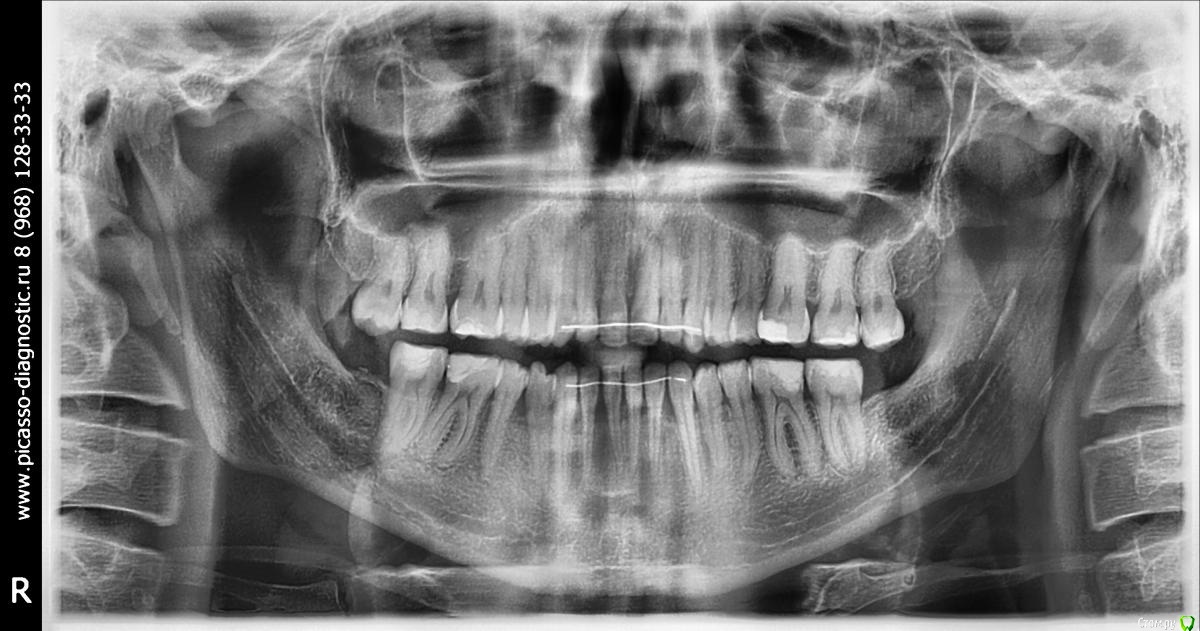

КТ https://yadi.sk/d/G5UP13aFRtrCaA

Здравствуйте, мне 29 лет, хочу остаться со своими зубами и не угробить ВНЧС.

В данный момент ситуация усугубилась, основные проблемы - множественные рецессии и хруст в ухе при глотании.

1ый Операция и только она. На вопрос поможет ли это устранить рецессию, был ответ, что вам никто не скажет, но для проведения операции нужно будет вернуть все зубы в прежнее положение.

2ой Провел диагностику, ТЭНС терапию, сделал капу на нижнюю челюсть (хруст при зевании прекратился, при глотании все равно слышно), про  рецессию было сказано, что некоторые зубы получают неправильную нагрузку, но причина именно множественной рецессии не в прикусе. Дальнейшие предложении - устранение перекрестного прикуса с помощью брекетов или оклюзионного протокола.